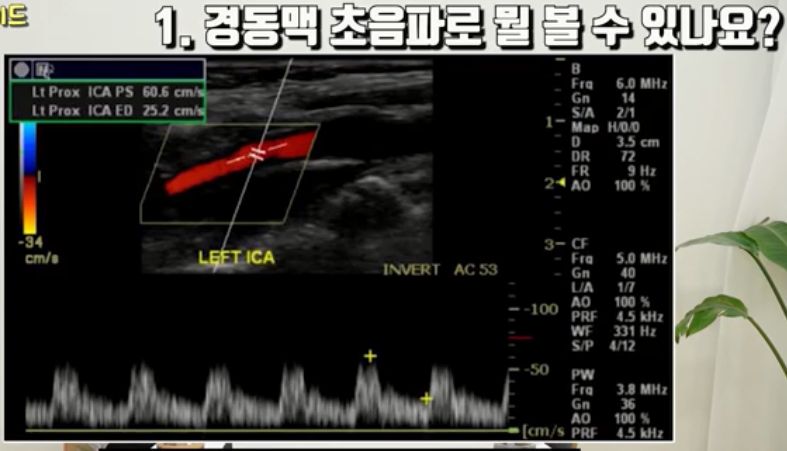

경동맥초음파검사 설명 /:/ 뇌혈관 협착증, 뇌졸중과 뇌졸중 약 설명 등 본문

경동맥 협착증, 동맥경화증, 혈전, 뇌졸중같은 질환과 관련

[신경검사실] 경동맥 초음파 검사 안내

가성비 최강 혈관 검사 l 경동맥 초음파에 대한 모든 것 [닥터인사이드] 2023

(의원에서) "5만원짜리 검사로 이런 것도 안다"